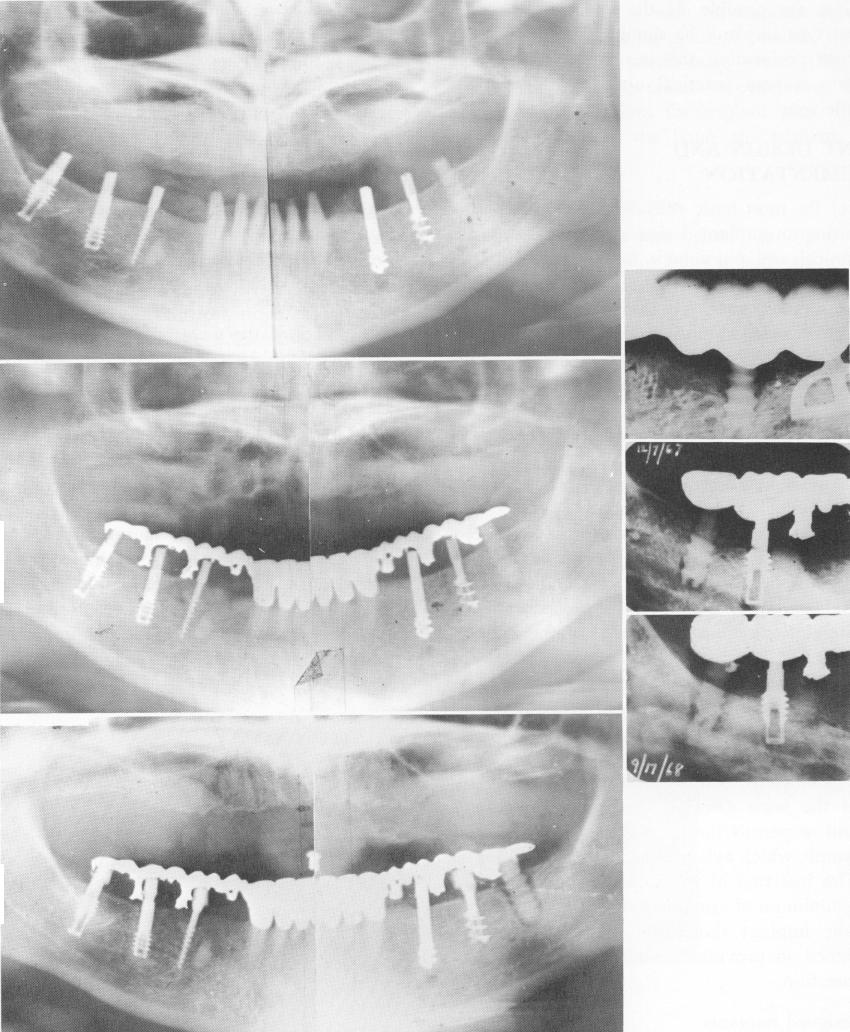

Fig. 14-6. A, Six different implants are seen in the same mouth. Left to right: Two Linkow titanium vent-plants, a narrow ridge (M. Chercheve) implant, a Chercheve spiral-shaft implant, a Muratori spiral implant, and a Sandhaus crystalline bone screw (aluminum oxide). The picture was taken immediately after the implants were placed. B, Three months later a breakdown of bone had started around the synthetic sapphire implant. C, Fourteen months postoperatively, the continued breakdown around the crystalline bone screw, but not around any of the others, is clearly shown. D, A blade-vent is acting as anchor tooth while the crystalline bone screw is anterior to it. Evidence of osteolysis is seen only around the anterior implant. E, Poorly trephined bone shows the holes around both implants made larger and deeper than their diameter. F, Two years later the bone has filled in around the deep portions of the vent-plant but not around the synthetic sapphire.